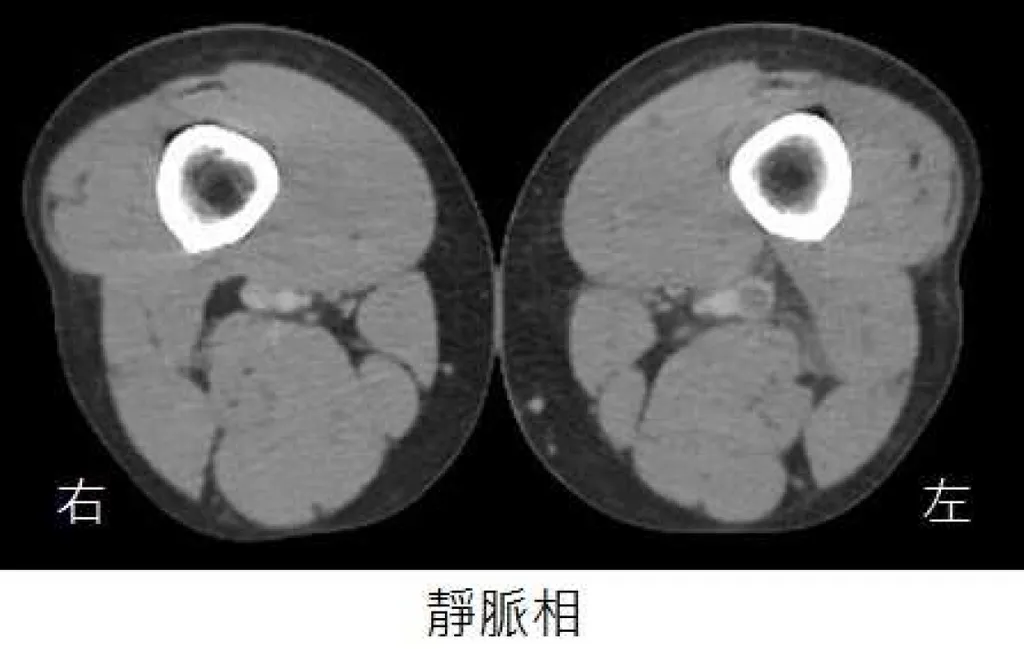

35 歲男性病人,主訴持續一星期的單側下肢腫脹,但無發燒症狀。雙側下肢靜脈注射顯影劑電腦斷層影像如圖所示,下列關於病況的敘述何者最恰當?

這題的解題核心在於從電腦斷層影像中辨識出深層靜脈栓塞(DVT),並理解其最嚴重的併發症。圖片中的靜脈相顯示左側股靜脈有顯影劑填充缺損,代表有血栓形成。